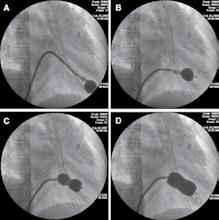

În cazul abordului retrograd, după obținerea accesului femural, se introduce o teacă arterială la locul de puncție. Concomitent se obține și un acces ve-

Figura 1. Variante de abord vascular utilizate pentru implantarea transcateter de valvă aortică – modificată [19]

nos periferic necesar pentru a introduce un electrod de stimulare temporară în ventriculul drept cu scopul de a realiza stimularea ventriculară rapidă necesară realizării valvuloplastiei aortice cu balon (VAB) și implantării protezei TAVI.[6]

Intervenția se realizează în condiții de anticoagulare cu heparină nefracționată 5000 U.I. Valva aortică este ascensionată retrograd prin sistemul arterial cu ajutorul unui fir ghid, urmat de un cateter de diagnostic pentru evaluarea gradientului transvalvular. În cazul protezelor de primă generație, se impune ascensionarea și a unui cateter de valvuloplastie cu balonaș pentru a efectua VAB anterior introducerii protezei. Valvele de ultimă generație pot fi implantate fără VAB prealabilă.

Implantarea valvei necesită o perioadă scurtă de stimulare ventriculară rapidă, cu o frecvență de aproximativ 160-220 de bătăi pe minut, pentru a reduce output-ul ventriculului stâng și a minimiza riscul de desprindere a balonului din tractul de ejecție sau de migrare a valvei. După predilatarea cu balon și poziționarea noii valve raportat la inelul aortic nativ, se procedează la implantarea protezei TAVI autoexpandabile sau expandabile prin gonflarea balonului în funcție de model. Gradientul transprotetic și fluxul valvular sunt evaluate atât anterior cât și ulterior implantării valvei, cel mai frecvent prin ecocardiografie transesofagiană. Cateterele și firele ghid sunt retrase, iar închiderea vasculară se realizează fie chirurgical, fie cu ajutorul unui dispozitiv de închidere percutanată. După intervenție, pacientul se recuperează și poate să se deplaseze în termen de 24-48 de ore.[4], [6] , [7]